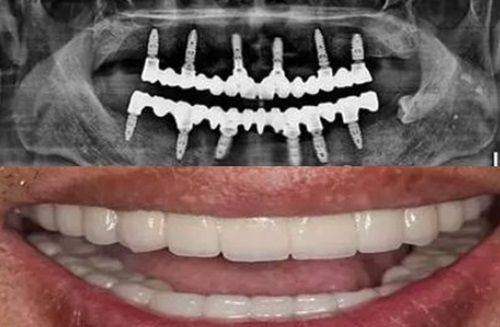

在硬件方面,三康口腔采用国内外进口品牌的牙科设备、补牙材料和种植体,和香港的菲腊牙科等具有影响力牙科机构采用相同品牌,确保了治疗的质量和成效。在软件方面,它拥有专精的医疗团队。推荐医生凌嘉蔚擅长龋病、牙体病诊断和治疗、美学嵌体修复、微创美学树脂修复以及牙体牙髓修复技巧,能为患者提供专精的治疗方案。